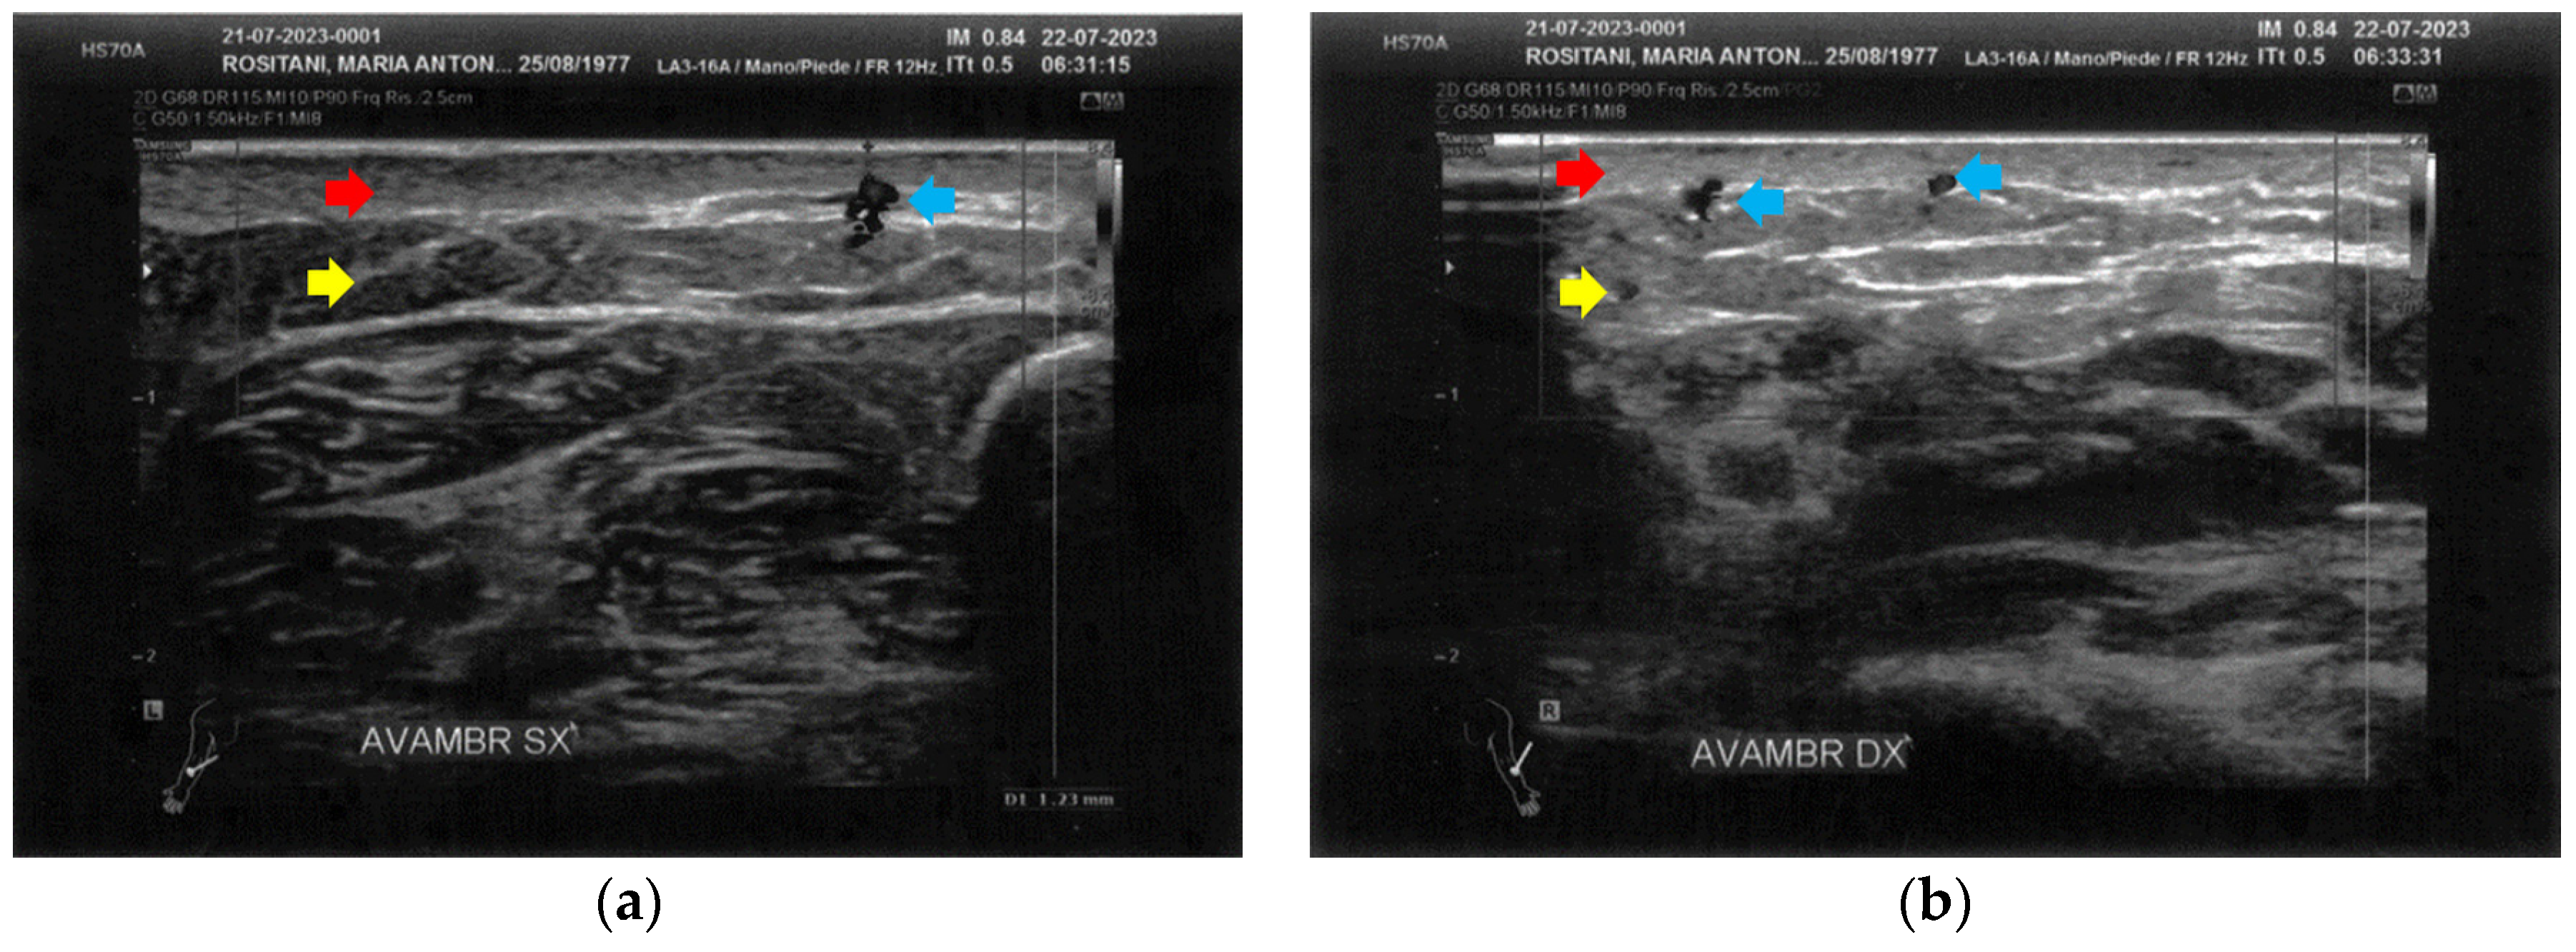

3.2. Imaging Evaluations After the Treatment